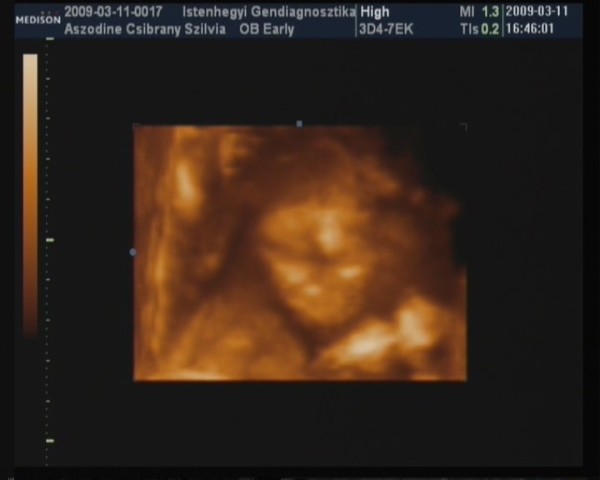

Minden rednben a Picurral és tuti FIÚ!!! :D :D :D

Kb 6 nappal korábbi a koránál igy vszinű átirom a vonalzómat hiszen múlt héten is ugyanennyinek mérték a korát, és a hosszabb ciklusaim miatt simán lehet.

Doki nagyon rendes volt mindent megmutatott majd ha lefényképezem akkor felteszek róla képet.Az arcát nagyon takarta igy nem nagyon tudtak róla szép képet feltenni,de majd májusban amikor megint megyünk 4d-re.